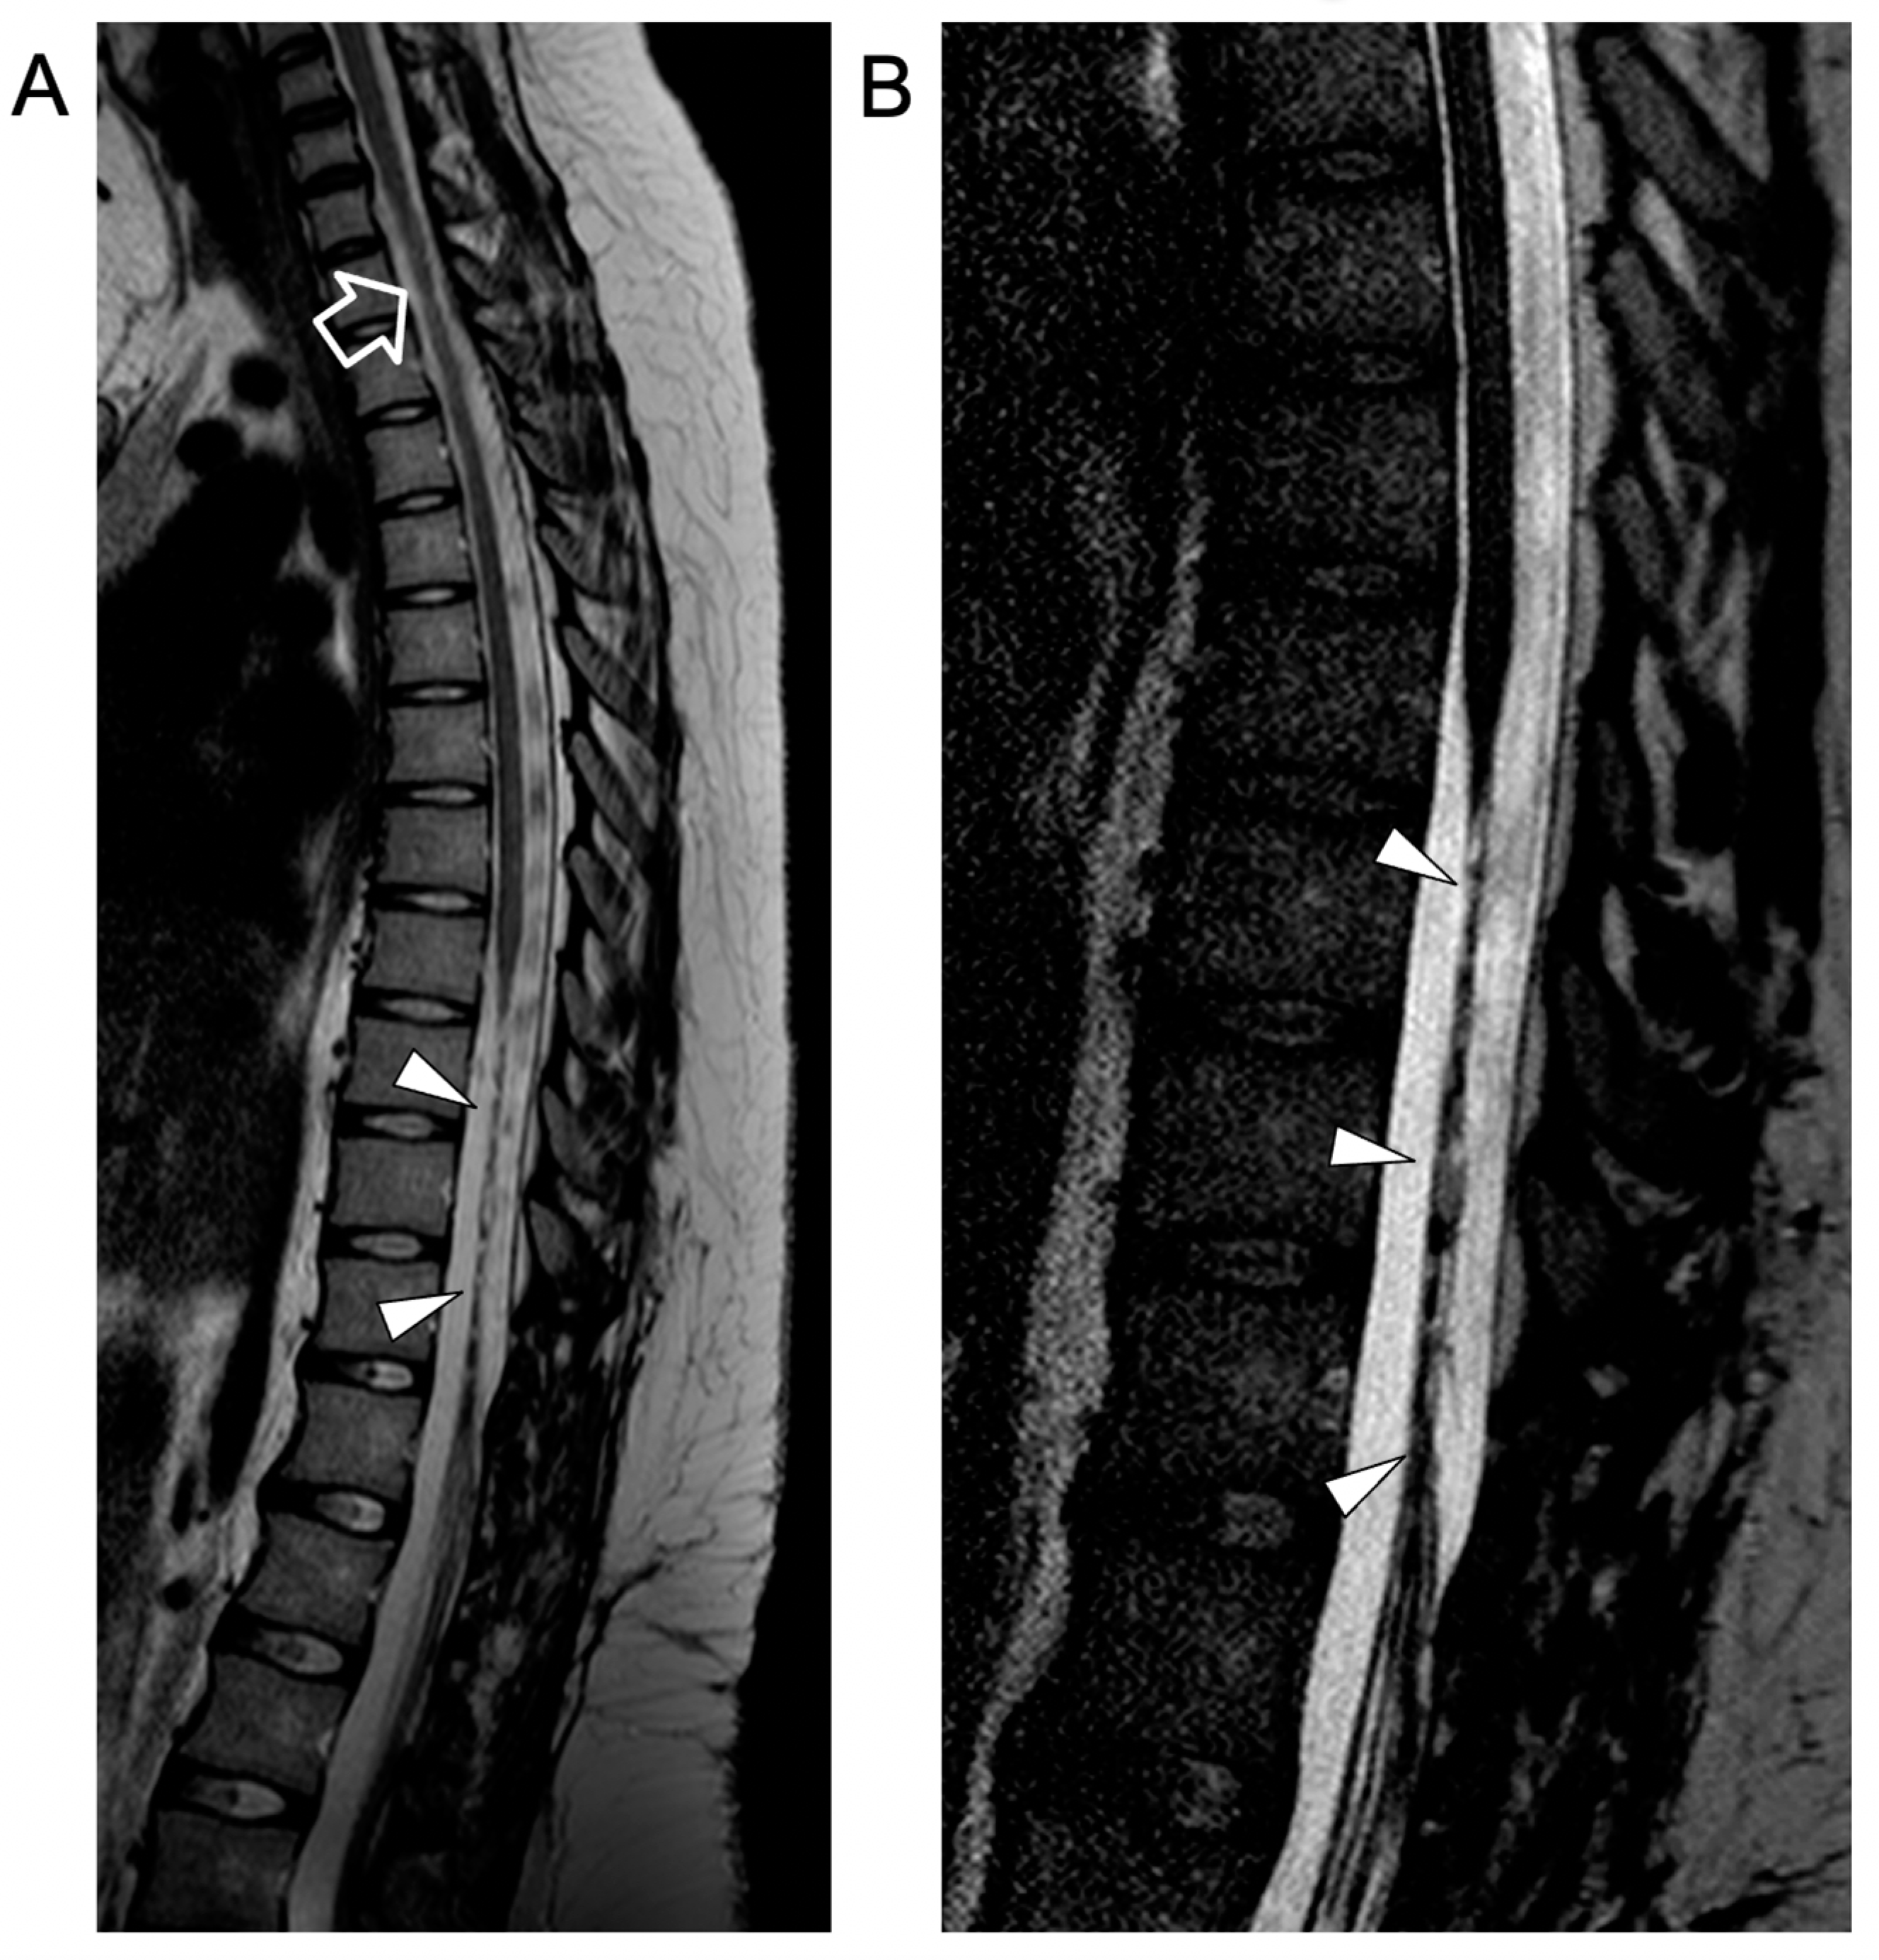

Figure 4.

Contrast-enhanced spinal MRI performed at the last follow-up, several months after clinical onset. Sagittal T2-weighted (A) and 3D driven equilibrium (DRIVE) (B) images reveal a focal area of mild spinal cord thinning at the superior dorsal level (empty arrow) and an extended segment of severe spinal cord atrophy in the inferior dorsal spinal level (arrowheads).